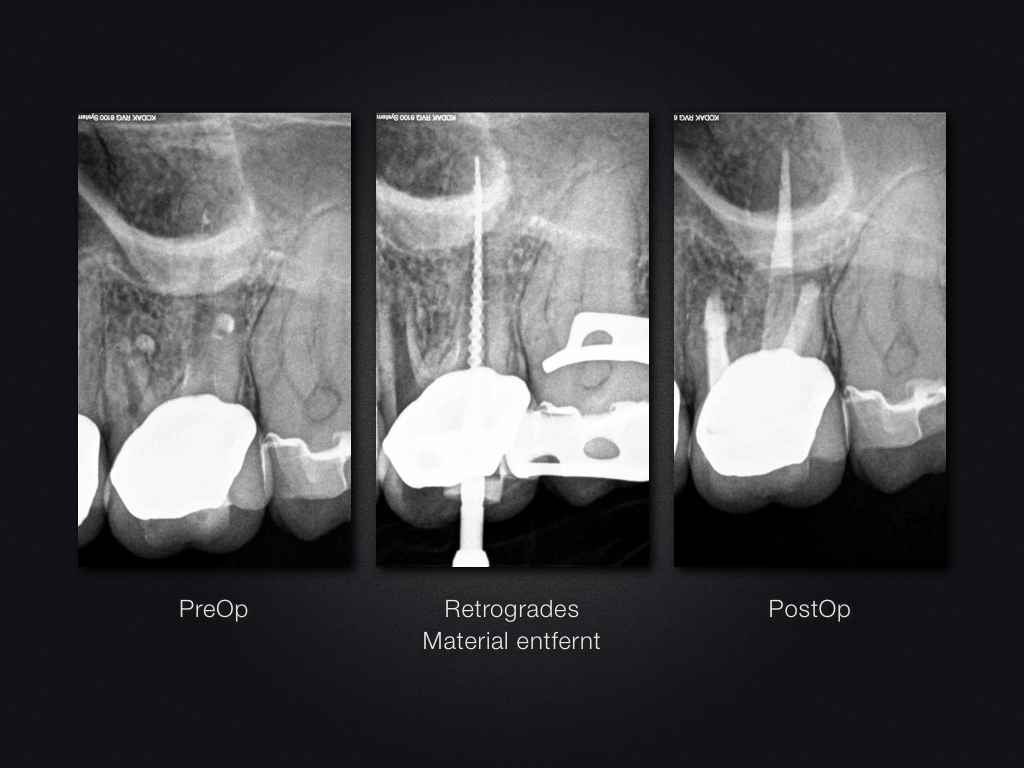

26D.009

2D vs. 3D (XXVI)